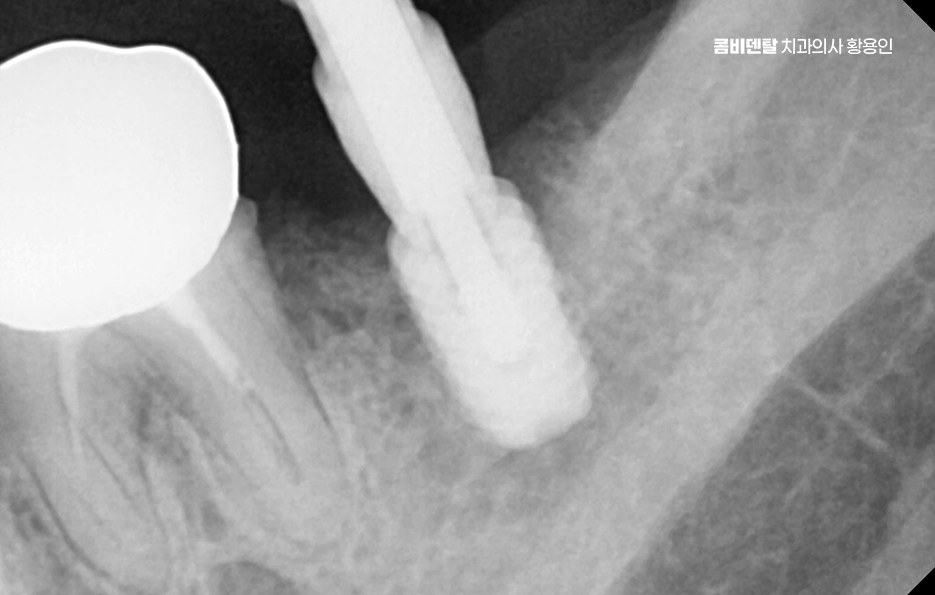

일반적으로 발치 후 뼈 상태가 양호하다면, 약 2~3 개월 정도의 치유 기간을 거친 다음 임플란트를 심게 되는데 요즘은 상황에 따라 바로 임플란트를 식립하는 ‘즉시 식립’ 방식도 많이 사용되고 있으며 단, 이러한 치료 방식은 뼈의 상태가 충분히 튼튼하고 염증이 없는 경우에 가능하며 경험 많은 치과의사와 함께하는 것도 중요할 수 있었어요

치아 발치 후 임플란트 치료 과정은 처음에 CT나 파노라마 엑스레이를 통해 뼈의 양과 밀도, 신경 위치를 정확히 확인하는 것부터 시작되며 치아가 빠진 자리에 뼈가 많이 흡수되어 있다면, 임플란트를 심기 전에 뼈이식을 먼저 해야 할 수 있지만 반대로 뼈 상태가 좋다면 임플란트를 심고, 보통 3개월 동안 뼈와 잘 붙을 때까지 골융합 과정을 기다리게 되며 골융합이 잘 이루어진 뒤에는 그 위에 지대주라는 연결 부품을 끼우고, 그 위에 최종 보철물을 씌우면서 치료가 마무리되고 있어요